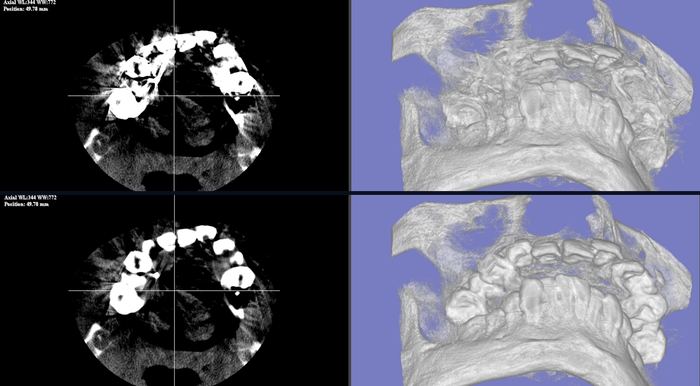

D-MAR金属アーチファクト低減

AIによるCT金属アーチファクト低減機能(D-MAR)。インプラントや 金属異物によるアーチファクトを自動検出・補正し、治療計画精度を向上させます。